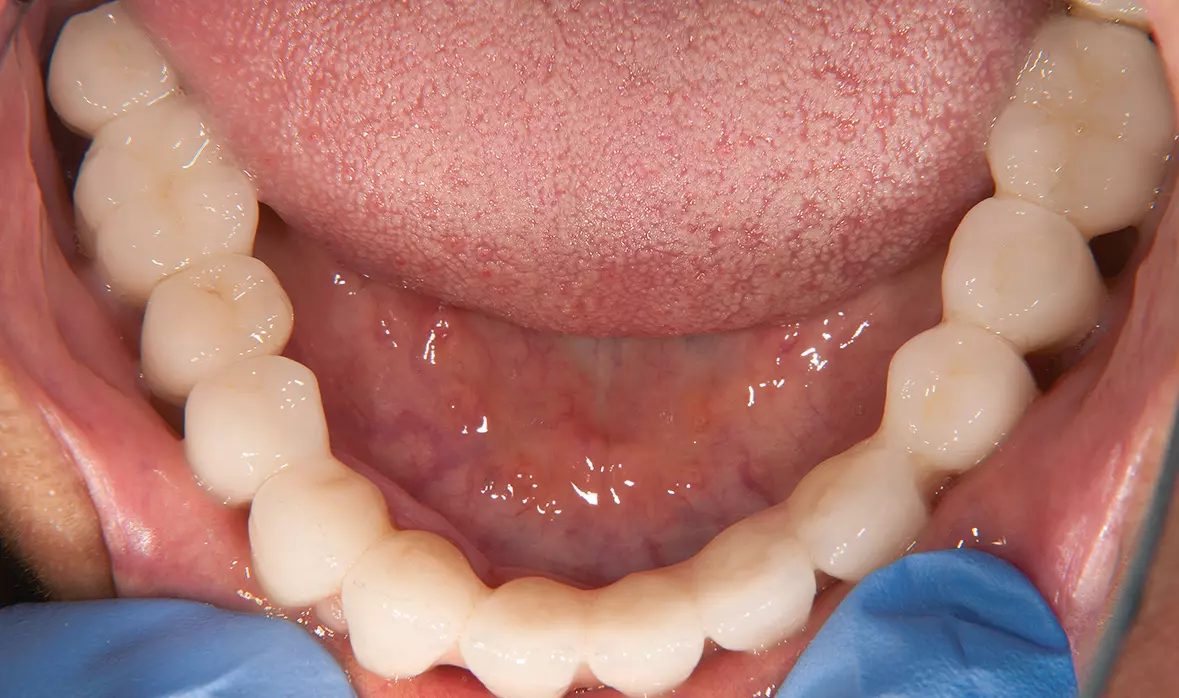

Abb. 46: Unterkieferversorgung. Dr. Michael Leistner

Abb. 46: Unterkieferversorgung.

Abb. 47: Gaumenfreiheit im Oberkiefer. Dr. Michael Leistner

Abb. 47: Gaumenfreiheit im Oberkiefer.